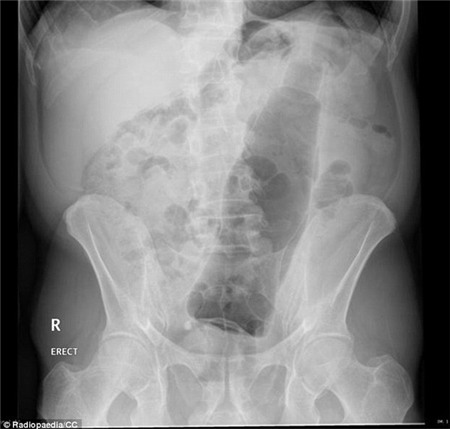

Ghê

hơn nữa, một bệnh nhân có hẳn một quả cà tím trong người. Quả cà tím

này đã gần ra đến hậu môn nhưng bất ngờ lại trồi lên khu vực đại tràng

và có thể lên cao hơn nữa.